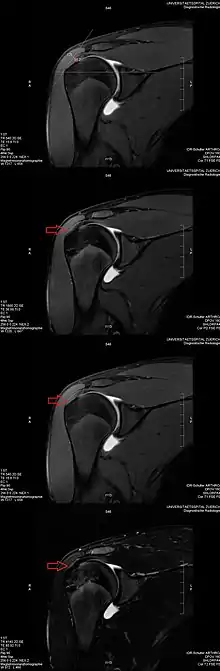

Application to medical imaging: The magic angle artifact

The magic angle artifact refers to the increased signal observed when MRI sequences with short echo time (TE) (e.g., T1 or proton density spin-echo sequences) are used to image tissues with well-ordered collagen fibers in one direction (e.g., tendon or articular hyaline cartilage).[1] This artifact occurs when the angle such fibers make with the magnetic field is equal to θm.

Example: This artifact comes into play when evaluating the rotator cuff tendons of the shoulder. The magic angle effect can create the appearance of supraspinatus tendinitis.